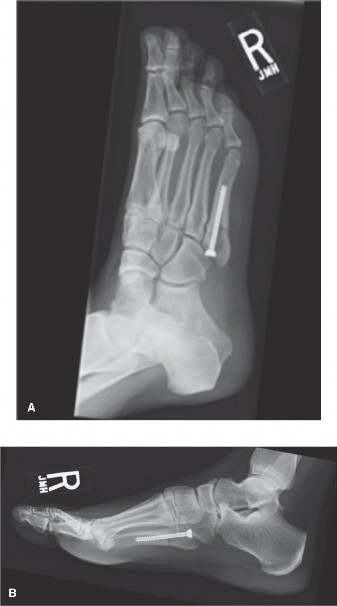

Image demonstrating intramedullary screw fixation of a fifth metatarsal fracture, with the screw centered within the medullary canal.